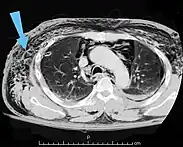

A chest X-ray of a right sided pulmonary contusion associated with flail chest and subcutaneous emphysema